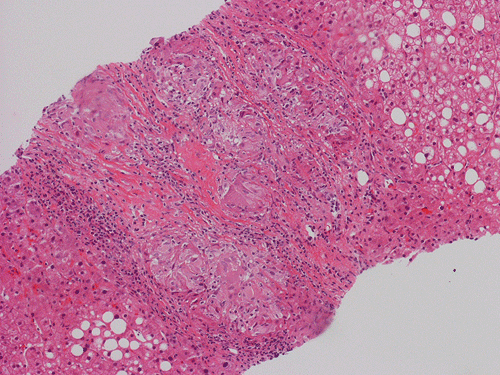

Pathology of the Case: At low magnification, a few small nodules (arrow in Panel A) can be seen with the hematoxylin and eosin stained section. On medium magnification, these nodules correspond to sharply defined granuloma without necrosis. These granuloma are not associated with a high density of lymphocytes in the surrounding liver parenchyma (Panel B and C). Multinucleated giant cells (arrow in Panel C, magnified in Panel D). On reticulin stain, there are reticulin fibers that extends into the granuloma (Panel E). Trichrome stain demonstrated bridging fibrosis (Panel F). The granuloma are well defined and some of them are surrounded by fibrous tissue (Panel G). Immunohistochemistry demonstrated preservation of bile ductules as well as proliferation of ductules (Panle H). No residual ductules are noted in the granuloma as revealed by immunohistochemistry for CK7 (Panel I). Neither acid fast bacilli or fungal organisms are identified by acid fast stain and Gomori's methenamine silver (GMS) stain.

Histopathologic features of sarcoidosis include scattered granulomas in the liver, which may tend to be portal or periportal. Multinucleated giant cells, epithelioid cells, and a variable but usually minimal inflammatory cellular response is present. The granulomas, like in sarcoidosis occuring in other organ systems, tend to be well-demarcated or "clear cut", several granulomas are often comparable in size, and necrosis is not typically present. Asteroid bodies, intracellular vacuolated structures resembling a sea anemone, may be found within the giant cells. Large basophilic, round to roughly oval, and concentrically laminated, Schaumann bodies may be evident in the sarcoid granuloma. None of these inclusions are pathognomonic feature of sarcoidosis, however, do suggest this diagnosis. Ductopenia, cholestasis and features of chronic cholestasis resembling PBC have been described in the cases of sarcoidosis. Severe fibrosis and cirrhosis in conjunction with portal hypertension may be present in sarcoidosis. End stage liver disease in sarcoidosis has been successfully treated by orthotopic liver transplant and recurrent disease has been reported in one such case. Reticulin fibers has a tendency to extend into the granulomas as illustrated in this case.